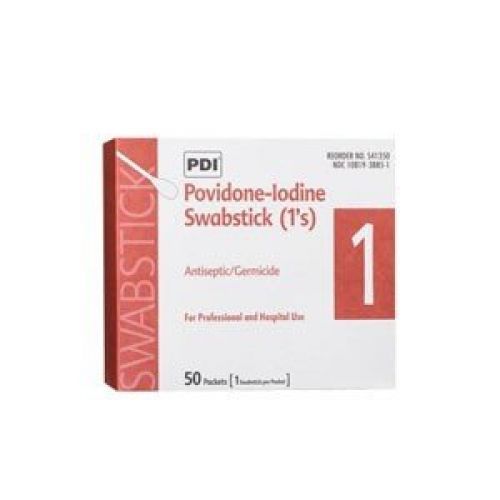

PDI PYB40600 - Pdi Inc. PVP Iodine Prep Pad, Medium, 1-1/5 x 2-3/5